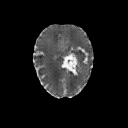

The goal of unsupervised anomaly segmentation (UAS) is to detect the pixel-level anomalies unseen during training. It is a promising field in the medical imaging community, e.g, we can use the model trained with only healthy data to segment the lesions of rare diseases. Existing methods are mainly based on Information Bottleneck, whose underlying principle is modeling the distribution of normal anatomy via learning to compress and recover the healthy data with a low-dimensional manifold, and then detecting lesions as the outlier from this learned distribution. However, this dimensionality reduction inevitably damages the localization information, which is especially essential for pixel-level anomaly detection. In this paper, to alleviate this issue, we introduce the semantic space of healthy anatomy in the process of modeling healthy-data distribution. More precisely, we view the couple of segmentation and synthesis as a special Autoencoder, and propose a novel cycle translation framework with a journey of 'image->semantic->image'. Experimental results on the BraTS and ISLES databases show that the proposed approach achieves significantly superior performance compared to several prior methods and segments the anomalies more accurately.